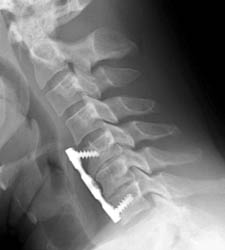

40 year old. male with history of falling off a truck while doing some work had

complained of low back pain, muscle spasm, hand and feet numbness, and neck pain

since the time of the action. Patient underwent C5-6 and C6-7 anterior cervical

discectomy with fusion using anterior plating.

Lateral film showing the intact plate and screws for the fusion and

nearly imperceptible grafting material in the disc spaces of C5-6 and C6-7. |

Lateral radiograph taken six weeks later on routine follow-up demonstrates

loosening of the superior anterior screws and ventral displacement of

the proximal anterior plate. Early incorporation of grafting material can be

seen at the disc spaces.